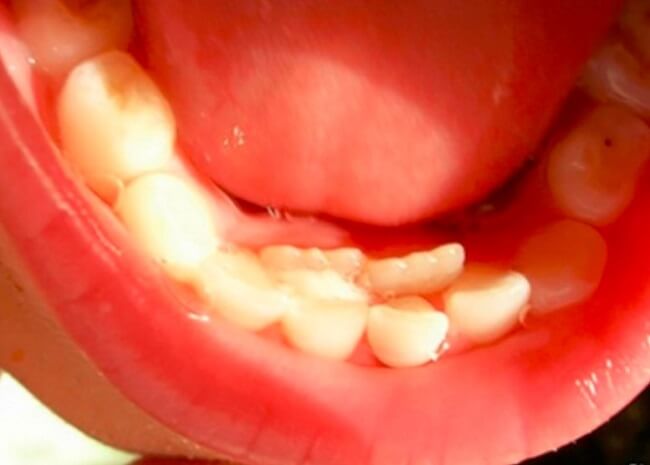

- Có thể xảy ra tình trạng răng vĩnh viễn mọc cùng lúc với răng sữa mọc chậm, tạo thành hiện tượng “hàm răng đôi”. Hậu quả là bé sẽ có hai hàm răng do răng sữa và răng vĩnh viễn tồn tại song song.